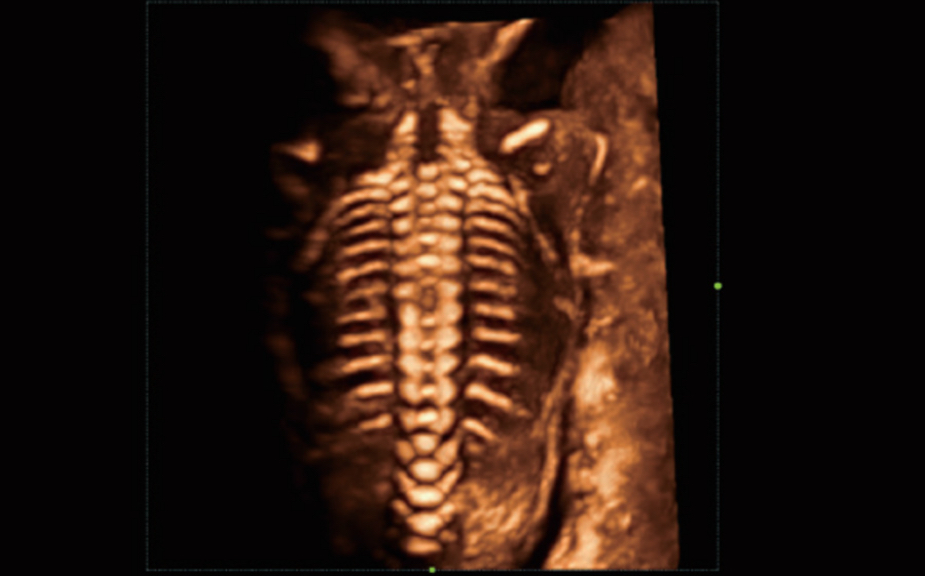

Obrazy kliniczne